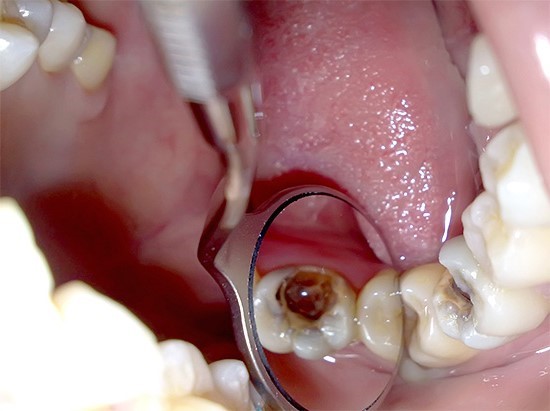

- 🔹 Định nghĩa: Viêm tủy răng xảy ra khi vi khuẩn phá vỡ cấu trúc răng và xâm nhập vào tủy.

- ⚡ Tủy viêm do lỗ sâu lớn hoặc răng nứt

- Khi vi khuẩn xâm nhập sâu vào tủy qua lỗ sâu hoặc vết nứt, tủy bị kích thích mạnh, áp lực trong tủy tăng, gây đau nhức dữ dội, đau nhói. Cơn đau thường tăng lên khi ăn, nhai, hoặc tiếp xúc thức ăn nóng/lạnh, và không giảm khi dùng thuốc giảm đau thông thường. Đây là lúc bạn cần điều trị tủy chuyên sâu tại nha khoa để loại bỏ vi khuẩn, giảm đau và bảo tồn răng.